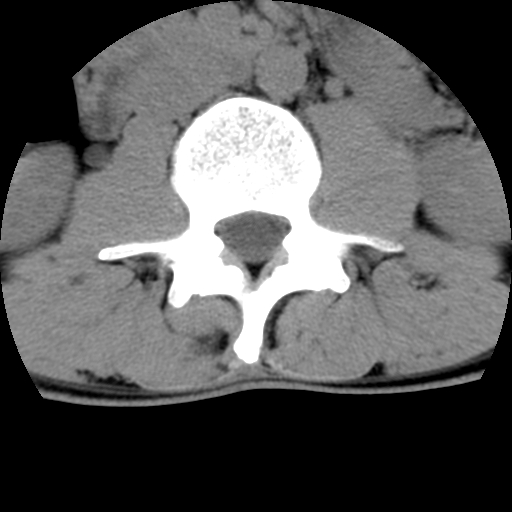

标题: CT16890:男,腰背痛.

男,腰背痛

本人诊断1tb2包虫,请会诊

1)右侧竖脊肌稍低密度肿块伴钙化(性质待定),不排除肿瘤可能;建议行进一步检查。2)腰椎间盘突出。

1.右侧竖脊肌软组织肿块伴团块状钙化,首先考虑血管瘤可能性大;建议行进一步检查;2。腰椎间盘突出。